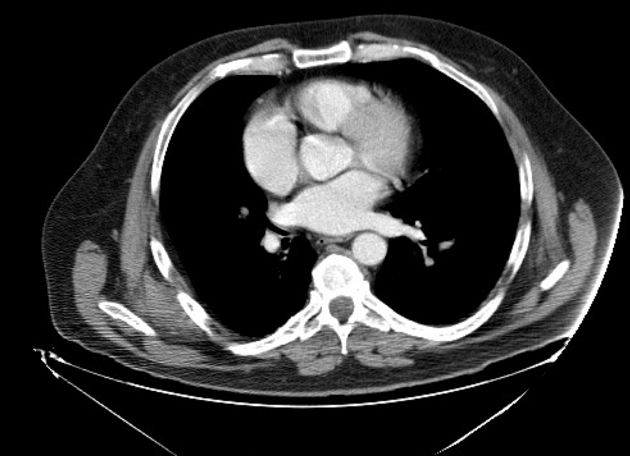

Diagnosis?

Rheumatoid arthritis.